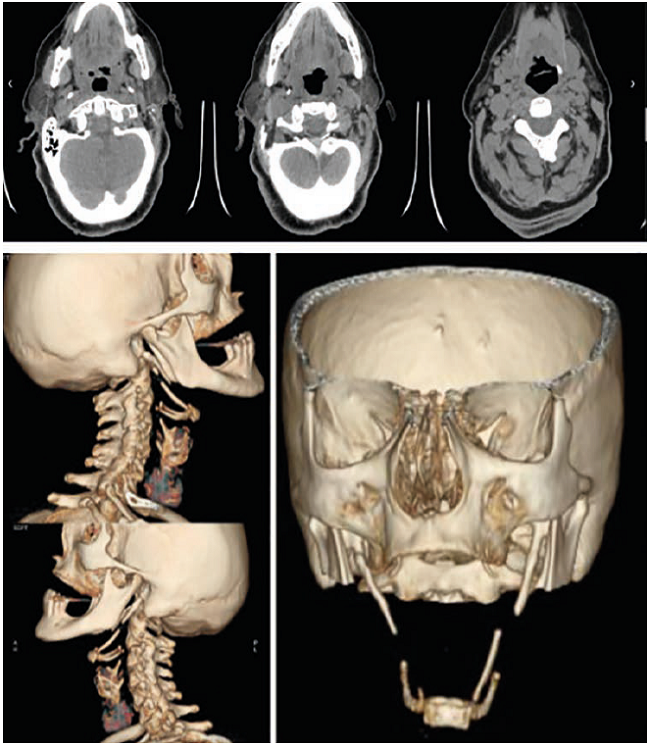

En una nueva tomografía computadorizada de cuello con reconstrucción tridimensional, se observó una apófisis accesoria en el lado izquierdo del hioides, así como elongación de la apófisis estiloides derecha y ausencia posquirúrgica de la izquierda. Sin embargo, existía la posibilidad de que el asta accesoria del hioides correspondiera a la osificación caudal del ligamento estilohioideo (figura 1).

El hallazgo patognomónico de esta entidad es una apófisis estiloides palpable a nivel de los pilares palatinos; sin embargo, esta exploración se hace con poca frecuencia durante el examen físico 2. En la mayoría de los casos, el diagnóstico se hace con ayuda de estudios imagenológicos (radiografía simple, tomografía computadorizada de cuello y resonancia magnética) o durante las necropsias. La tomografía computadorizada de cuello con reconstrucción tridimensional es el estudio de elección para llegar al diagnóstico, como en el presente caso 2,4,9,11.